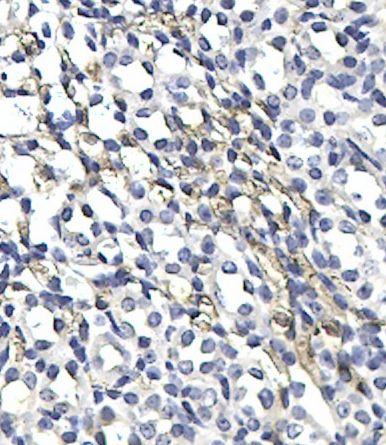

帮忙看看这个免疫组化染色做得怎么样?